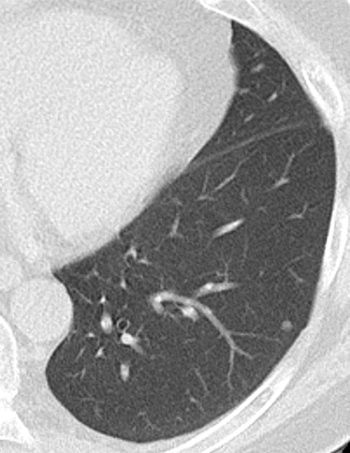

低被ばく肺CT検査のご案内

2024年のがん死亡数1位は肺がんで約7万5千人を超えています

【出典:国立がん研究センターがん情報サービス「がん統計」(厚生労働省人口動態統計)】

早期に発見して治療することにより肺がんで亡くなることを防ぐことができます。

自覚症状のないうちから検診を受けること重要です。早期肺がんは自覚症状がありません。

低線量CTとは?

通常のCTよりも被ばく線量を1/7に減らしながら、胸部X線画像では見逃されやすい早期の小さな肺がんや肺の異常を発見できる検査です。検査時間は5分程度です。

こんな方におすすめします

☆喫煙者、過去に喫煙歴のある方

1日の喫煙本数×喫煙年数が600以上の重喫煙者の方は低線量CT検査に死亡率減少効果があり、1年に1回の検査が強く推奨されています

【出典:国立がん研究センター 肺がん検診ガイドライン2025年度版】

☆40歳以上の方

☆同居家族に喫煙者がいる(受動喫煙の可能性がある)方

☆建設工事現場などで粉じんや石綿のばく露のある(あった)方